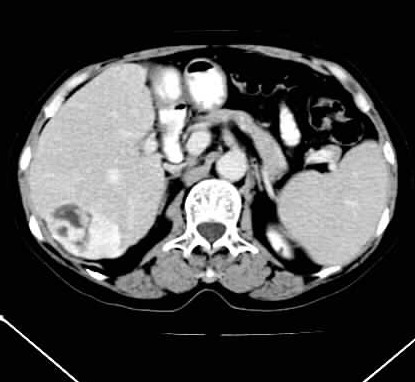

标题: CT24035:肝内占位

肝右叶后段低密度块影,增强后造影剂逐渐向病灶充填,支持肝血管瘤。